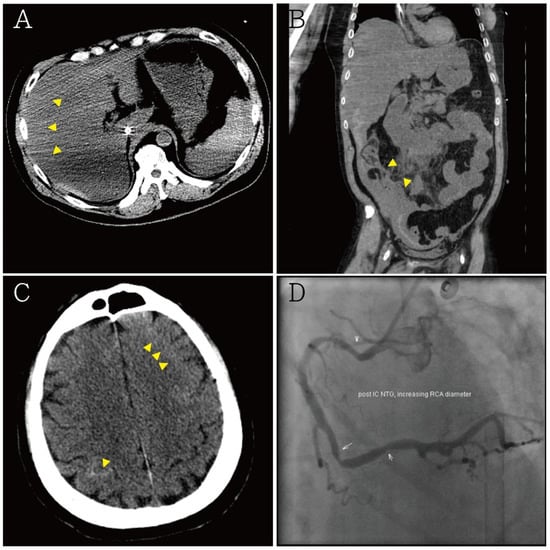

2. Case Presentation